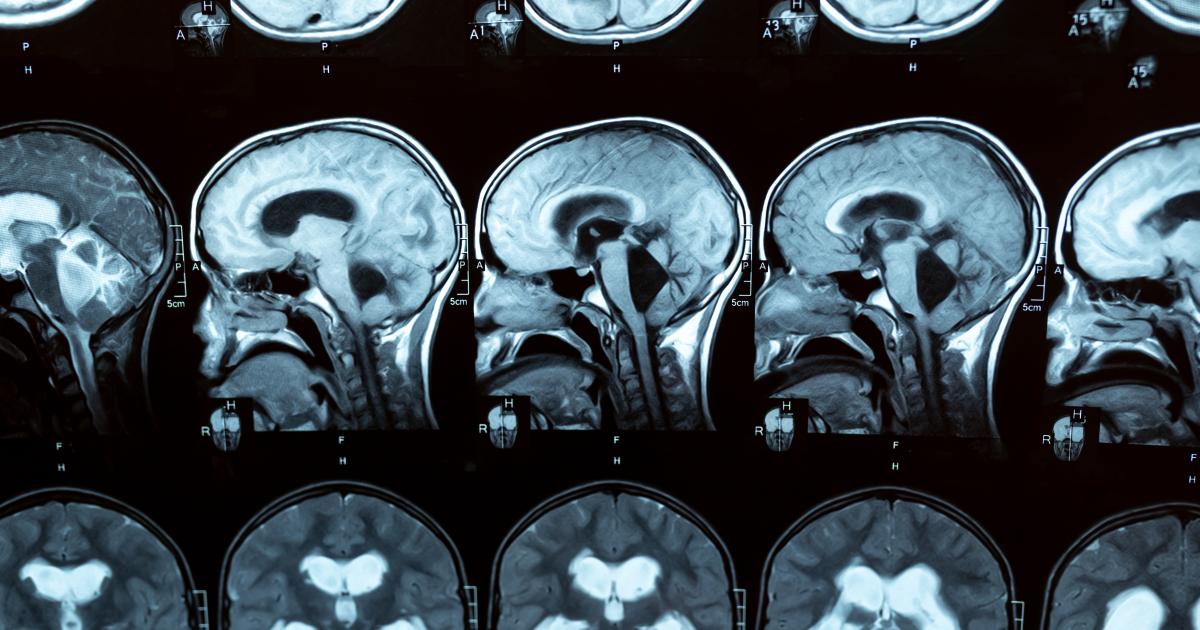

Hydrocephalus scans

Hydrocephalus refers to a build-up of excess fluid in cavities in the brain (called ventricles), causing them to enlarge and possibly increase pressure on the brain. It’s far from uncommon around the world. In the US, around 1 in 500 babies are born with hydrocephalus, with more developing the condition in the first two years of life (the figures for Europe are not directly comparable but are available here). Nor is it restricted to children: in adults the condition can occur at any time, particularly after an intracranial infection or bleeding, or after the age of 60, with increasing prevalence with age. In fact, it is quite likely to be underdiagnosed in this age group, when symptoms may be ascribed to Alzheimer’s or Parkinson’s disease. Which of course means that many people – up to 10% of dementia patients  – could be living with a treatable condition, not a degenerative one. Just think of what that could mean for quality of life, not only for the sufferers, but for their loved ones and carers.